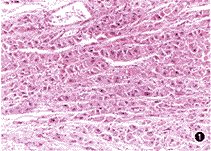

FLC多發生於無硬變的肝臟,腫瘤大多位於左肝葉,常為單個,瘤界清晰,邊緣呈扇形質地硬,剖面見纖維間隔橫貫瘤體;鏡下可見瘤細胞呈巢團狀,部分呈相互吻合的瘤細胞索,周圍有緻密的纖維組織呈板層樣包繞,瘤細胞較大,呈立方或多角形,胞漿豐富,呈強嗜酸性,核仁明顯,瘤組織內血竇豐富(圖1)。

(1)H-E染色可見瘤細胞漿內有豐富的強嗜酸性顆粒。

(2)膠原纖維和纖維母細胞平行排行呈板層狀包繞巢狀索狀或片狀分布的瘤細胞群。